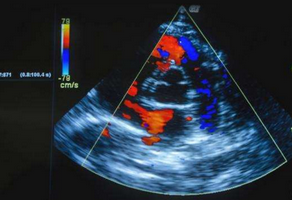

心臟彩超檢查全稱心臟彩色多普勒超聲檢查,與磁共振、CT、同位素掃描并稱為現(xiàn)代醫(yī)學四大影像診斷技術(shù)。無論是先天性心臟病還是后天形成心臟病,心...